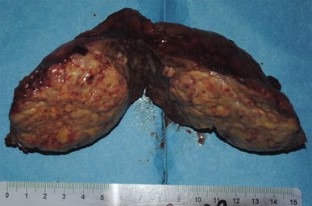

Combined hepatocellular carcinoma and cholangiocarcinoma (cHCC–CC) is a rare form of primary liver cancer (PLC). It is difficult to make a correct preoperative diagnosis of cHCC–CC because of the lack of special features of the disease. We here present a case of a 68-year-old man who presented with fluctuant fever, chills, and sweating and was eventually diagnosed as cHCC–CC after surgery. The tumor was 6.0 cm in diameter with distinct borders and no satellite lesions or lymph nodes were observed during macroscopic examination of the resection specimen. The fever resolved in the postoperative period till the 28th day after surgery, when the patient developed extensive abdominal metastases and died shortly after. More attention should be paid to the patient with PLC showing abnormal features such as FUO, normal range of tumor markers, atypical imaging, and less cirrhosis. Hepatic resection is the treatment of choice although with short-term outcomes.

Fig. 1